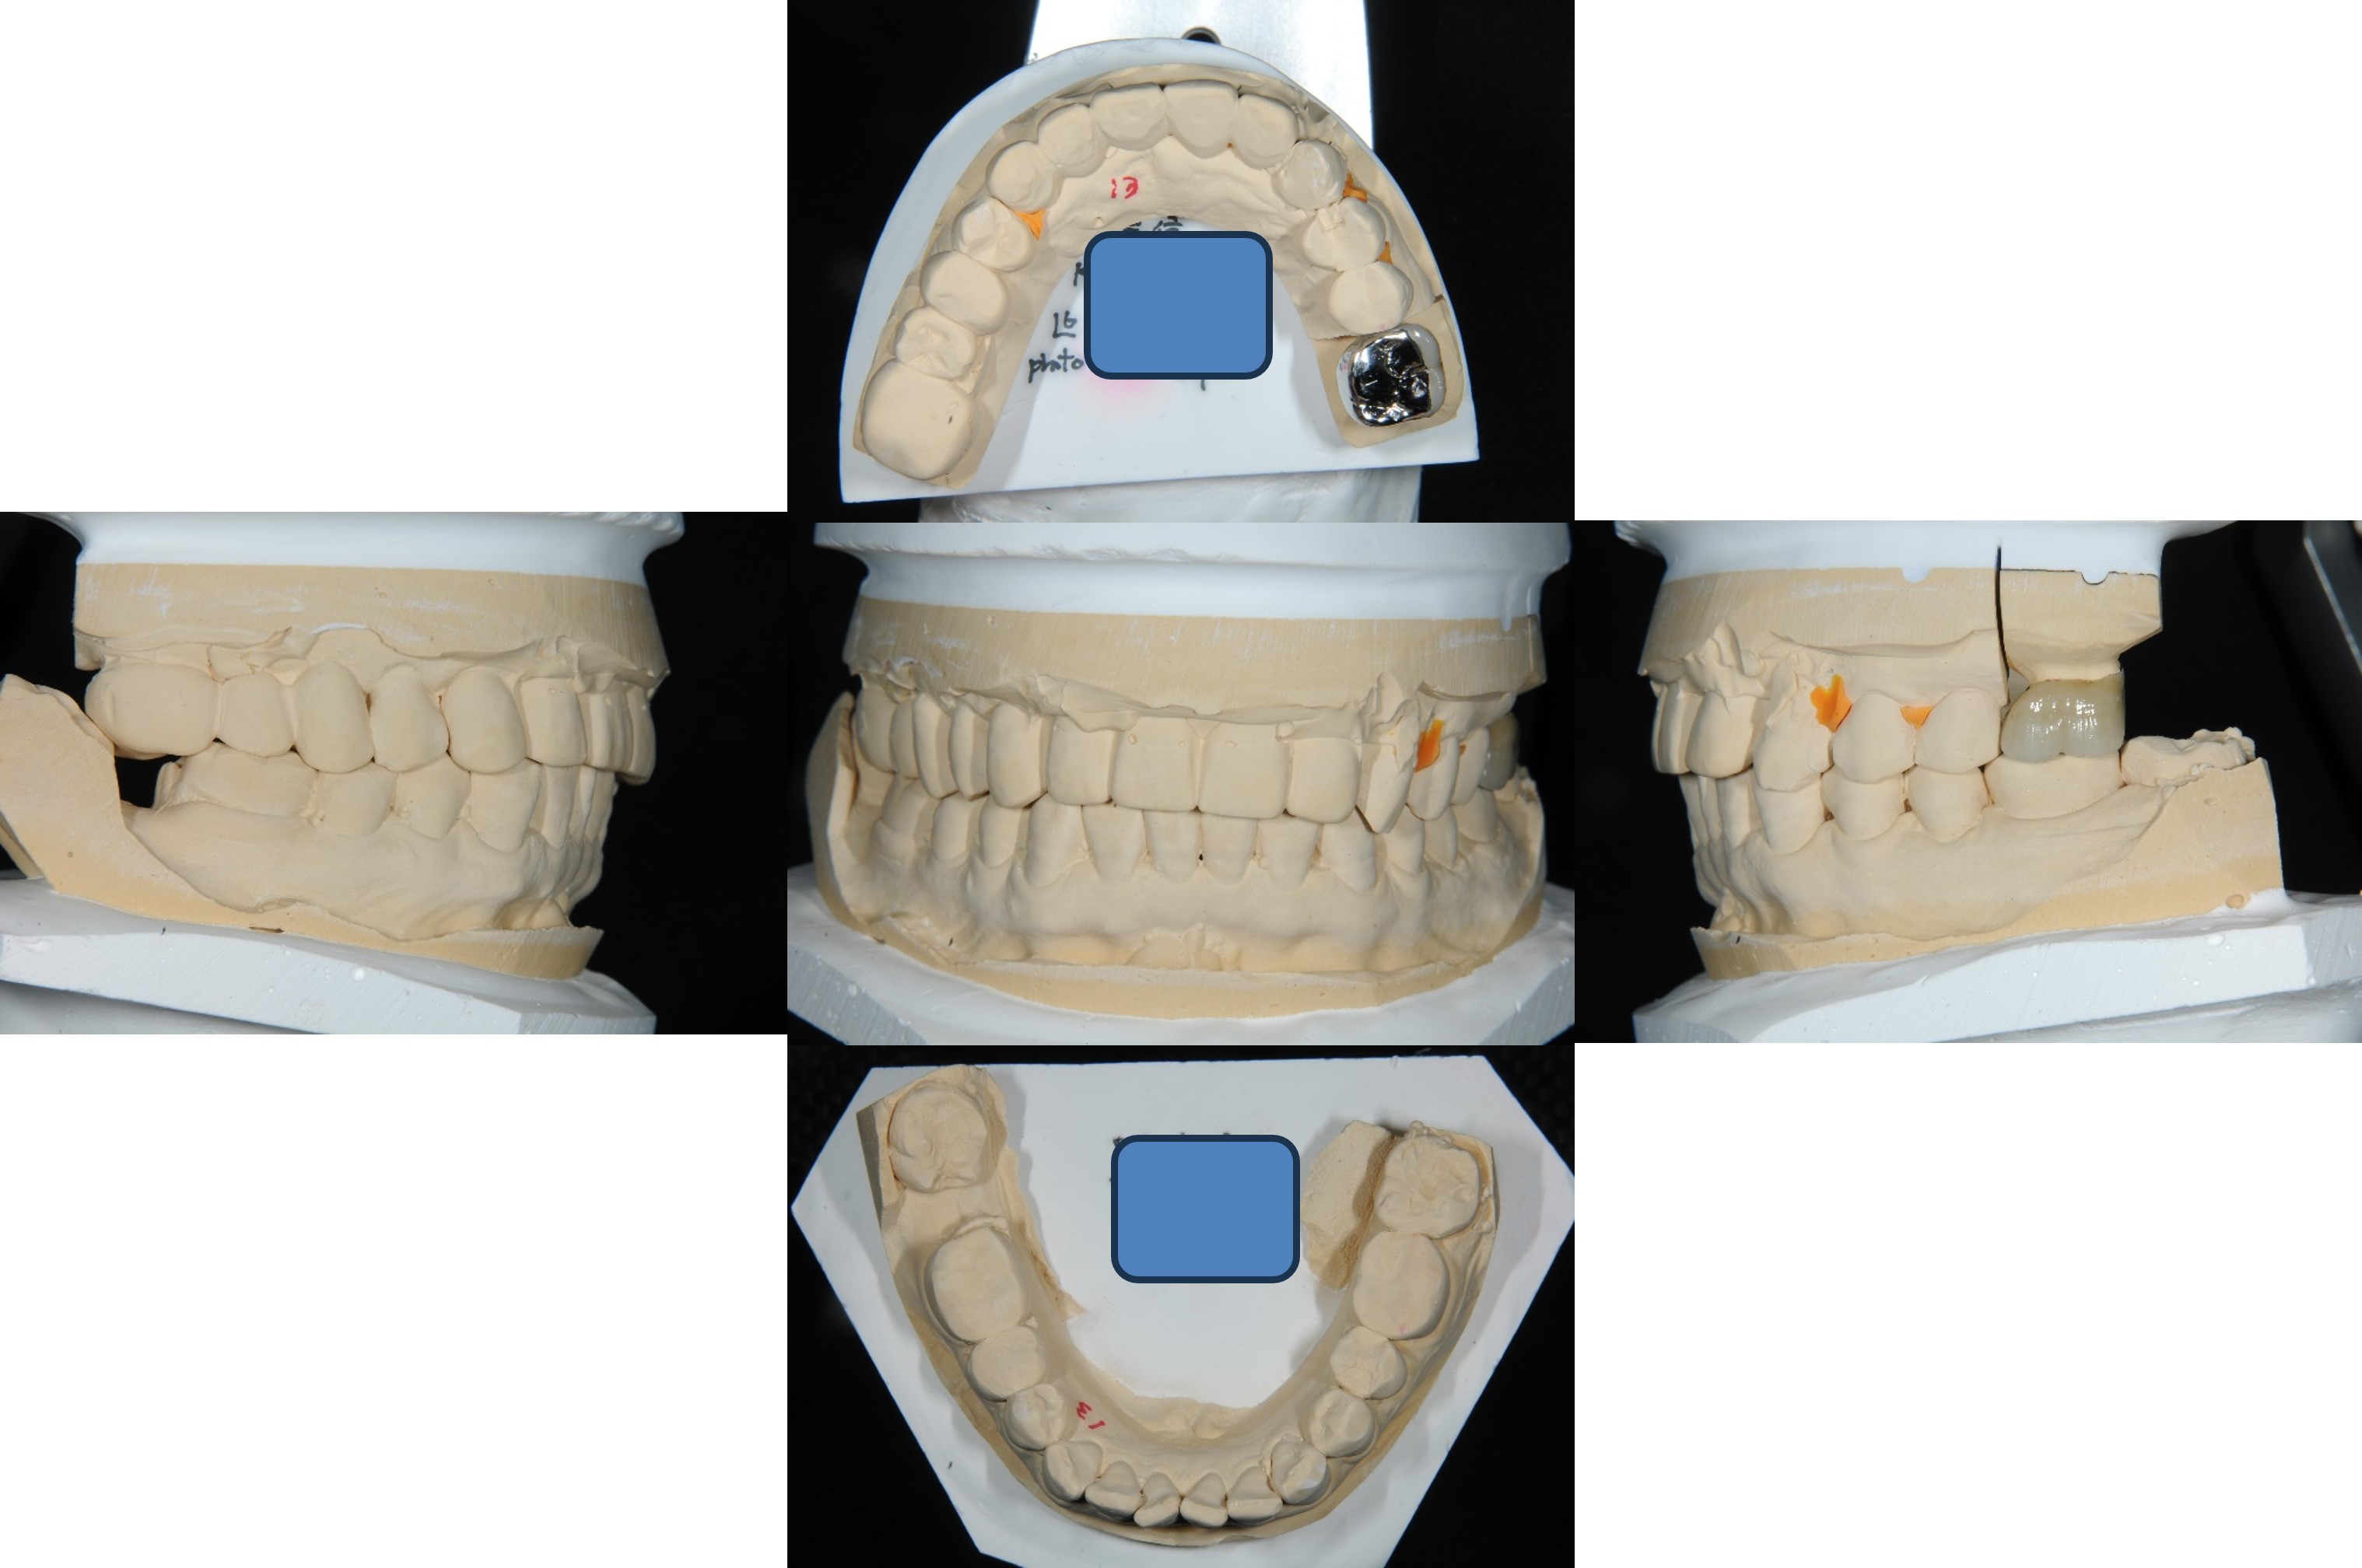

上面弓、上咬合器

技師於咬合器製作金屬燒付瓷牙

考量咬合面,製作金屬面之金屬燒付瓷牙